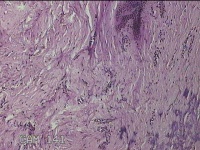

右下腹部切口结节

发现右下腹部切口结节10余年。

灰白暗红色带皮肤样结节2.3x1.3x0.8cm一个。表面糜烂,切面灰白色,质硬。

需要侵袭性纤维瘤病和纤维瘢痕鉴别一下